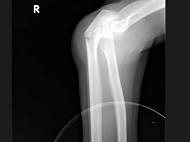

问题 女,55岁,跌倒后右手痛,结合X线平片表现,正确的诊断是?(?)

选项 A.柯莱斯骨折 B.蒙泰贾骨折 C.加莱阿齐骨折 D.尺桡骨骨折 E.反柯莱阿齐骨折

答案 B